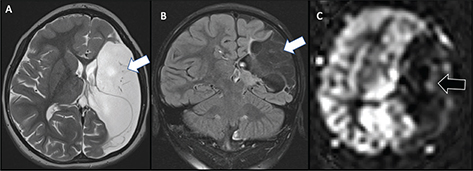

On MRI, acute infarcts demonstrate reduced diffusivity within minutes, exhibiting high signal on DWI and low computed diffusivity on ADC maps (Figure 5) (46). Diffusivity remains reduced for about 6 days, peaking at about 3 days, before pseudonormalization occurs, with diffusivity then increasing to above normal by the second week (4750). Timing of DWI changes can be affected by the age of the patient, size of the stroke, and how quickly collateral blood flow is recruited. DWI also detects early or pre-wallerian degeneration in infants (also referred to as “acute network injury”), characterized by injury to the antegrade white matter tracts following acute infarct and manifests as reduced diffusivity in white matter pathways affected by the infarction within a few days of the injury (Figure 5) (51). Common pathways affected by acute network injury include the corpus callosum, thalamus, and descending corticospinal tract. When seen along the corticospinal tracts, acute network injury is highly predictive of poor motor outcomes (52, 53).

Fig 5

Figure 5. Acute neonatal arterial ischemic infarction in a three-day-old girl with seizures. Axial DWI (A) and (B), and axial ADC (C) images show extensive area of reduced diffusion in the left MCA territory (arrows). Arrowheads (A, B, C) indicate pre-Wallerian degeneration in the posterior limb of the internal capsule and left cerebral peduncle along the corticospinal tract. D. 3D time-of-flight MRA shows abrupt absence of flow in the left MCA (arrow). Axial T2-weighted image (E) at 5-month follow-up shows extensive encephalomalacia and volume loss in the left MCA territory. Case courtesy of Dr. Tamara Feygin, Department of Radiology, Children’s Hospital of Philadelphia.